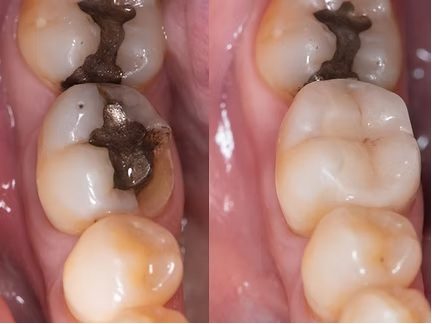

Amalgamsanierung

auf unsere biologische Art

Amalgam ist eine quecksilberhaltige Metalllegierung, die aufgrund möglicher allergener Eigenschaften sowie aus ästhetischen Gründen heute zunehmend kritisch betrachtet wird.

Als Alternativen kommen moderne Werkstoffe wie Kunststoff, Keramik oder Gold infrage. Wir beraten dich hierzu individuell und umfassend hinsichtlich Haltbarkeit, Verträglichkeit und Ästhetik.

Amalgamfüllungen können heute in der Regel sicher und unproblematisch durch zahnfarbene, amalgamfreie Restaurationen ersetzt werden. Die Entfernung erfolgt unter speziellen Schutzmaßnahmen wie Kofferdam (Spanngummi) und Absaugtechniken.

Begleitend zur Amalgamsanierung kann eine gezielte Ausleitung von Schwermetallen sinnvoll sein, um den Körper bei der Entgiftung zu unterstützen. Hierfür bieten wir eine spezielle Amalgamausleitung an.